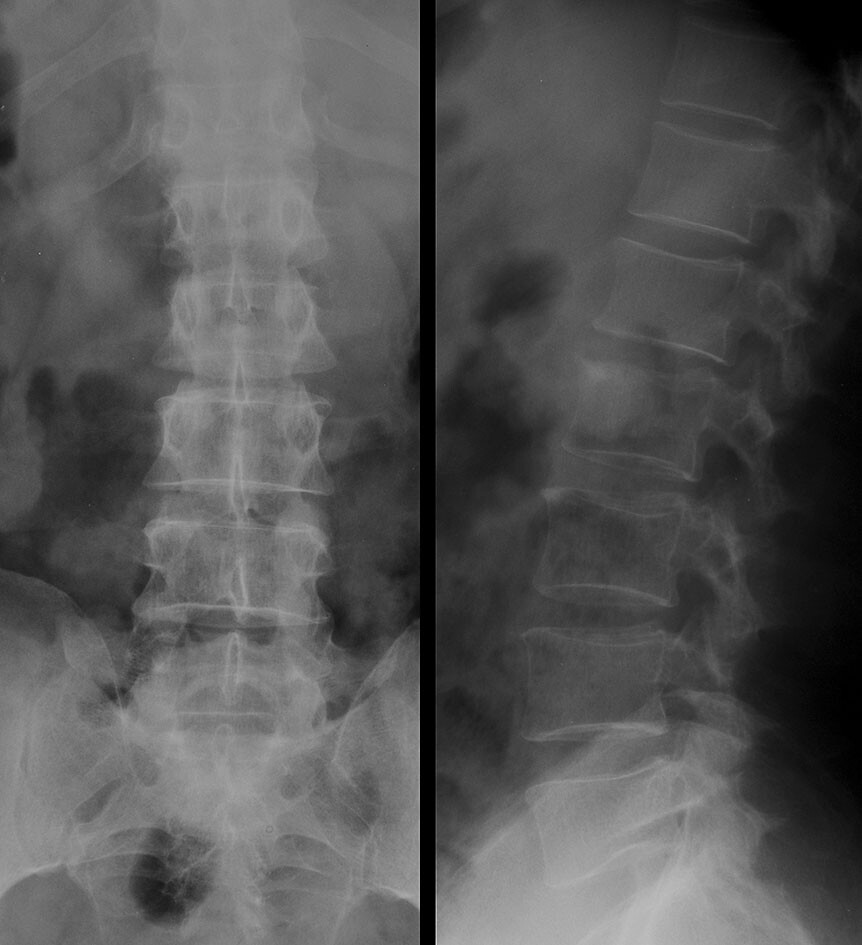

From www.flickr.com

Bacterial osteomyelitis & disciitis, spine XR (1 of 2) Flickr Bacteria In Osteomyelitis Osteomyelitis is an inflammatory bone disease that occurs when the bone is disrupted or exposed to bacteria that can cause. Common symptoms are localized bone. Certain bacteria such as adhere to the bone by expressing receptors, called adhesins, for some. Osteomyelitis is inflammation and destruction of bone caused by bacteria, mycobacteria, or fungi. Unsurprisingly, the most prevalent organism in polymicrobial. Bacteria In Osteomyelitis.